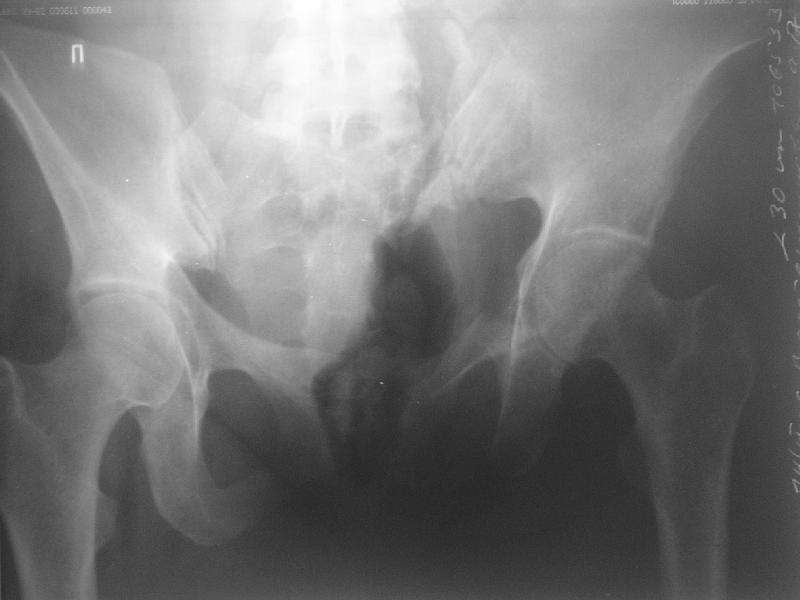

Прооперировали молодую девушку 32 лет спустя 9 мес после травмы.

Имелся стойкий болевой синдром, неопороспособность левой н/конечности, моторные и сенсорные нарушения в левой голени и стопе, патологическая подвижность левой половины таза. Первым этапом закрыто в аппарате исправили деформацию ( в течении 2,5 нед). Вторым закрытое введение илиосакральных винтов в крестец (канюллированные 7,2 мм Chm) + туннелизация зоны псевдоартроза спицама Киршнера, реконструкция передних отделов таза, накостный остеосинтез . Аппарат частично демонтирпован, оставлена "передняя рама" После устранения деформации отмечен регресс неврологической симптоматики, уменьшение болевого синдрома. Интересующие вопросы: 1. Прогноз для сращения псевдоартроза крестца. 2. сроки нагрузки весом левой половины таза. Буду очень признателен за ваши мнения по этому поводу.A female 32 y.o. admitted to our unit 9 months after initial injury with pain, inability to bear weight at the left lower limb, sensor and motor disturbances in the left foot and tibia, with mobility of the left hemipelvis.At first closed reduction was performed by an external fixator within 2,5 weeks. After correction her pain decreased and some neurological progress was achieved. Now two iliosacral screws 7,2 mm were inserted, and anterior lesion was fixed by a plate. External fixator was partially unmounted, only anterior frame left in place.Images attached.How would you evaluate chances of healing of the sacrum with the current position?When would you allow weight-bearing of the left leg?THX in advance.